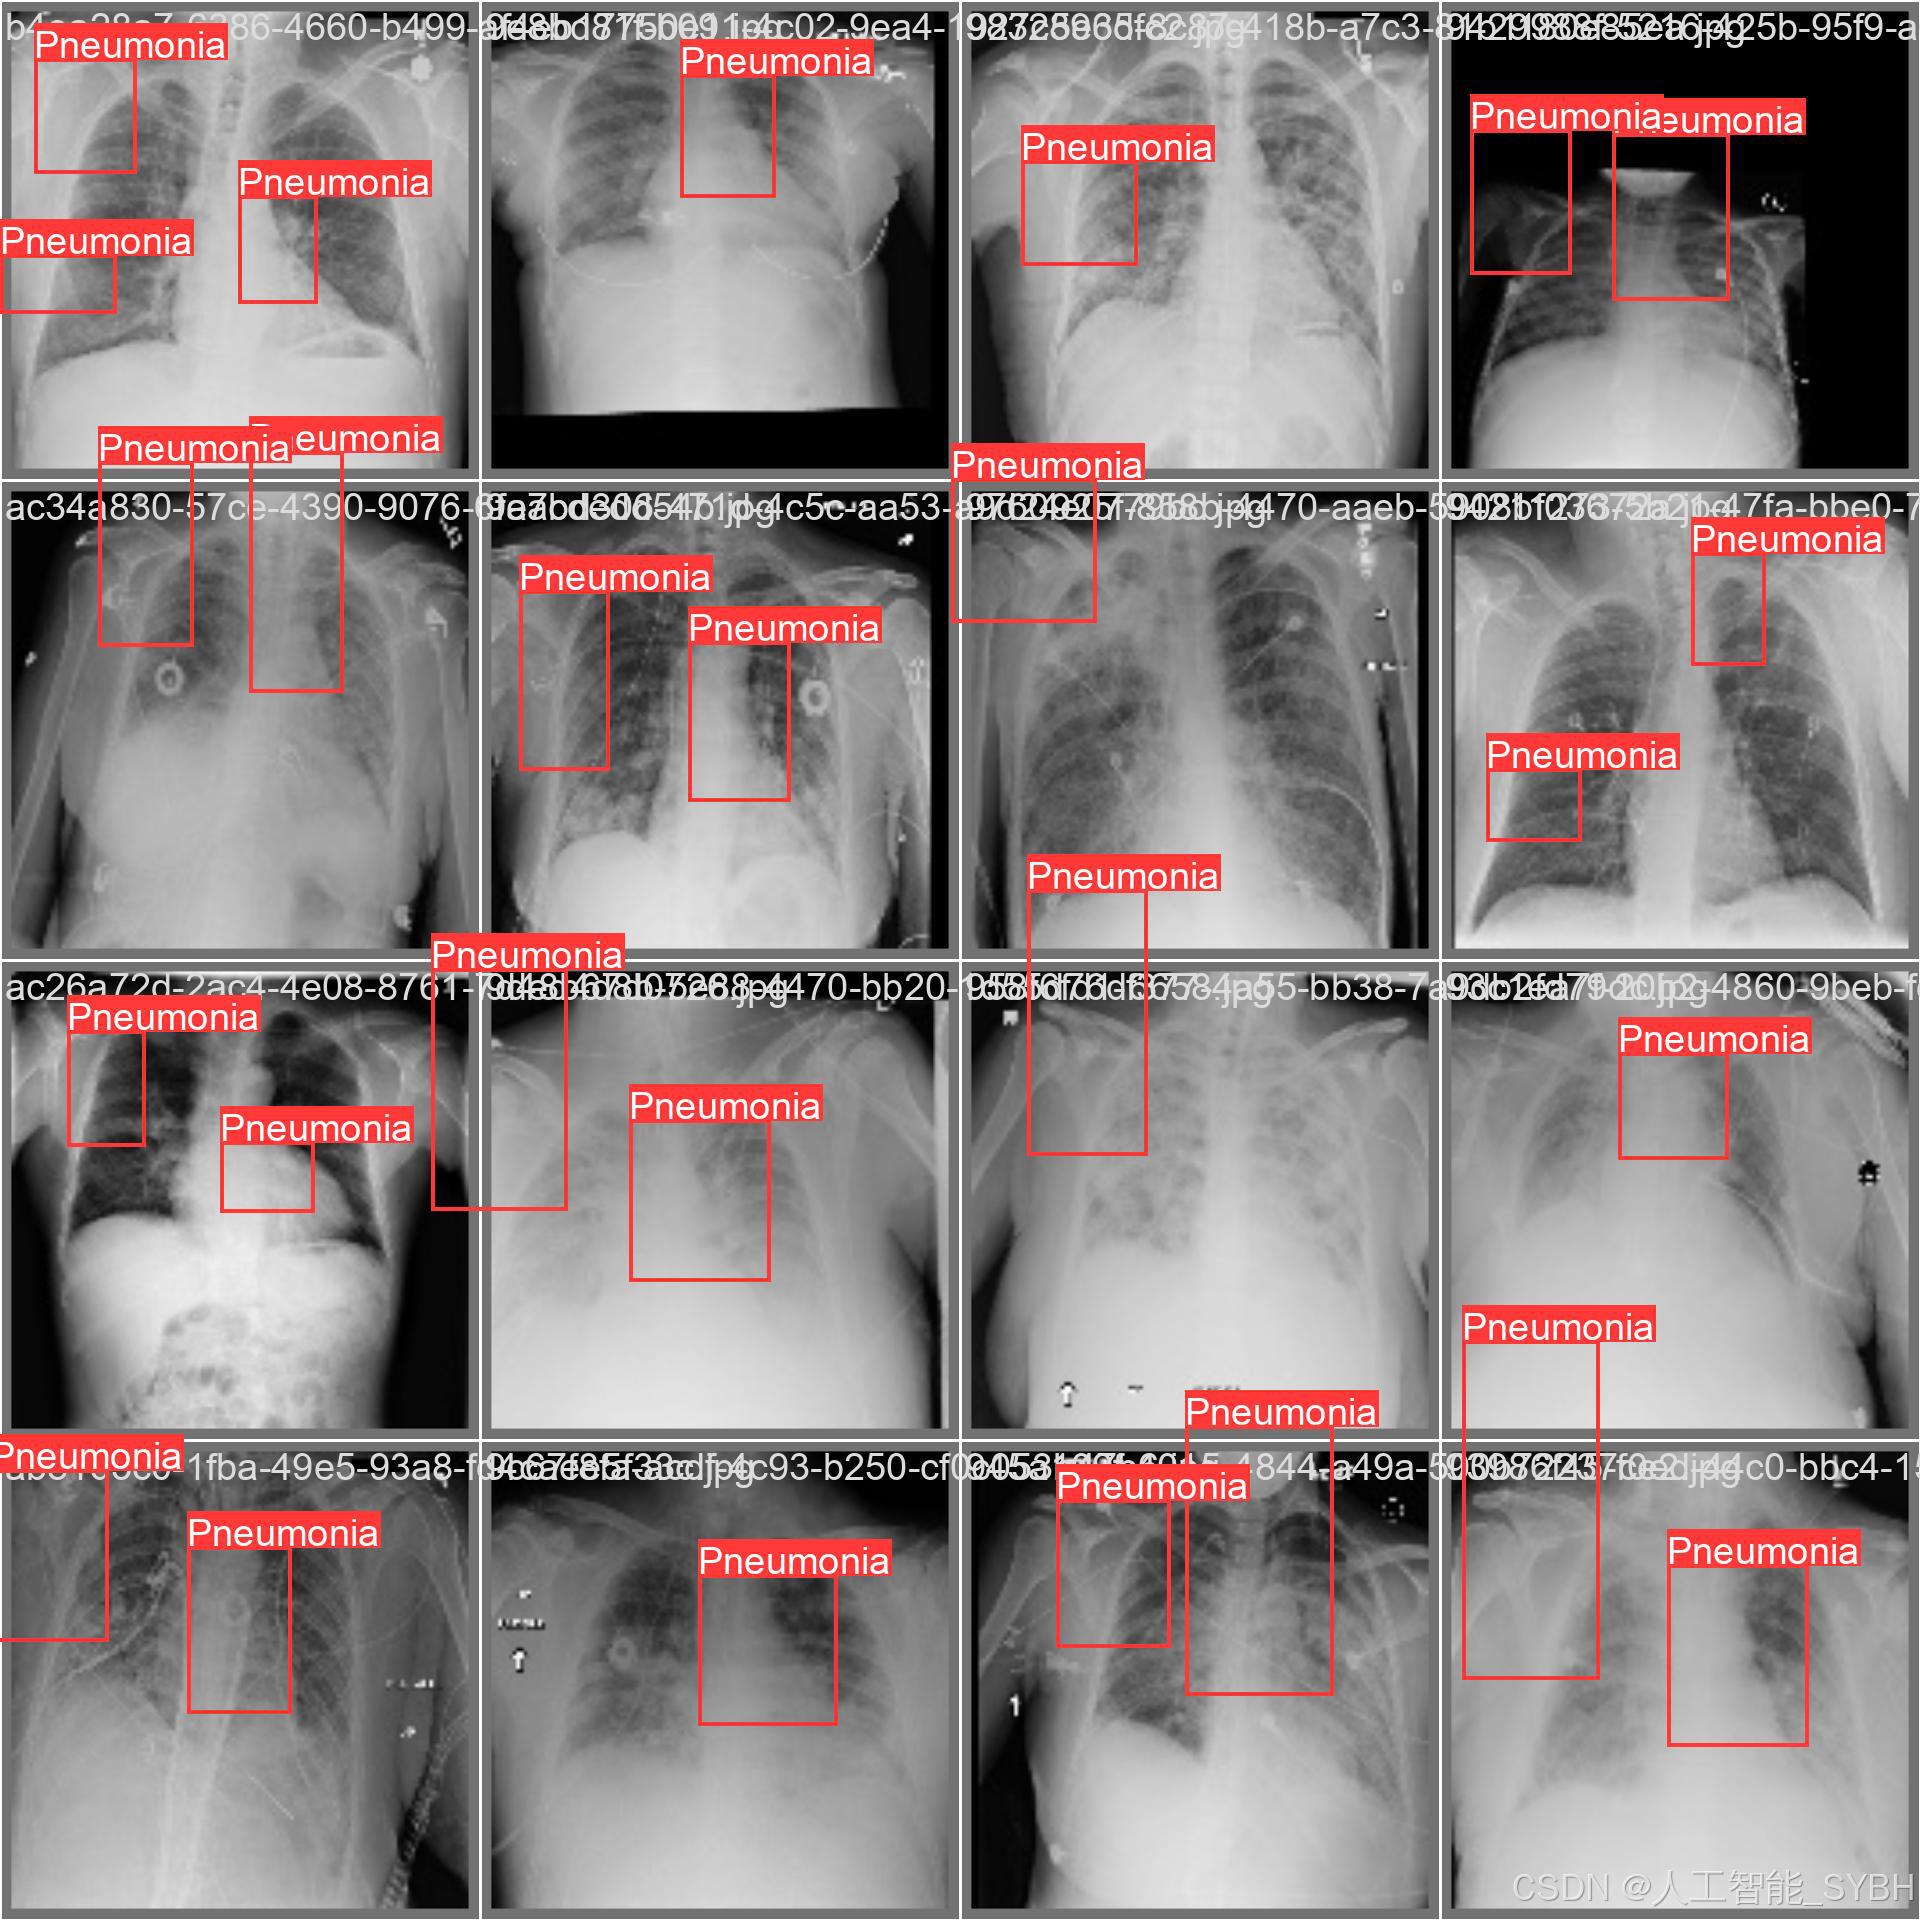

本项目基于YOLOv8深度学习框架,开发了一套高效、准确的肺炎智能检测系统,用于医学影像(如X光或CT扫描)中的肺炎识别。系统针对单类别('Pneumonia'肺炎)进行优化,采用包含3,772张训练图像、539张验证图像和1,078张测试图像的数据集进行训练和评估。该系统能够快速、自动地识别肺炎病变,辅助医生进行诊断,提高医疗检测效率,减少漏诊和误诊风险。

本项目基于YOLOv8深度学习框架,开发了一套高效、准确的肺炎智能检测系统,用于医学影像(如X光或CT扫描)中的肺炎识别。系统针对单类别('Pneumonia'肺炎)进行优化,采用包含3,772张训练图像、539张验证图像和1,078张测试图像的数据集进行训练和评估。该系统能够快速、自动地识别肺炎病变,辅助医生进行诊断,提高医疗检测效率,减少漏诊和误诊风险。

本系统利用计算机视觉和深度学习技术,实现了对肺炎影像的高精度检测,适用于临床辅助诊断、远程医疗筛查和大规模流行病监测等场景。相比传统人工阅片方式,该系统能够大幅缩短诊断时间,提高检测一致性,并降低医疗资源消耗,具有重要的临床应用价值。

✅ 图片检测:可对单张图片进行检测,返回检测框及类别信息。

✅ 批量图片检测:支持文件夹输入,一次性检测多张图片,生成批量检测结果。

图片检测

该功能允许用户通过单张图片进行目标检测。输入一张图片后,YOLO模型会实时分析图像,识别出其中的目标,并在图像中框出检测到的目标,输出带有目标框的图像。批量图片检测

用户可以一次性上传多个图片进行批量处理。该功能支持对多个图像文件进行并行处理,并返回每张图像的目标检测结果,适用于需要大规模处理图像数据的应用场景。